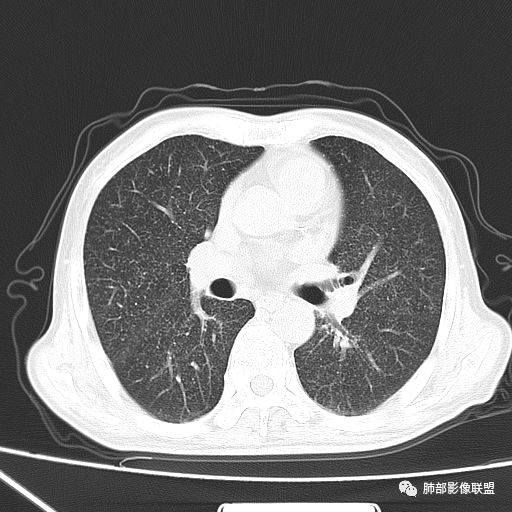

2019年9月12日CT(外院片,手机拍摄)

2019-10-20复查CT如下:

两肺弥漫性粟粒样结节伴左上肺小结节,呈三均匀分布,有结核的临床表现,支持血性播散性肺结核。

大小、分布均匀,边缘清楚

细小结节,弥漫,撒米粒样——血道来源

部分可见分支状

血道来源的病灶,均匀、细微,而且部分有分支状,都符合粟粒型肺结核

急性血行播散型肺结核  两肺广泛分布粟粒大小的结节状密度增高影,具有大小均匀、分布均匀、密度均匀的典型“三均匀”特征,注意急性血播病灶非常小,一般粟粒影直径1~2mm。

病灶密集者出现肺外围血管影不清或减少。